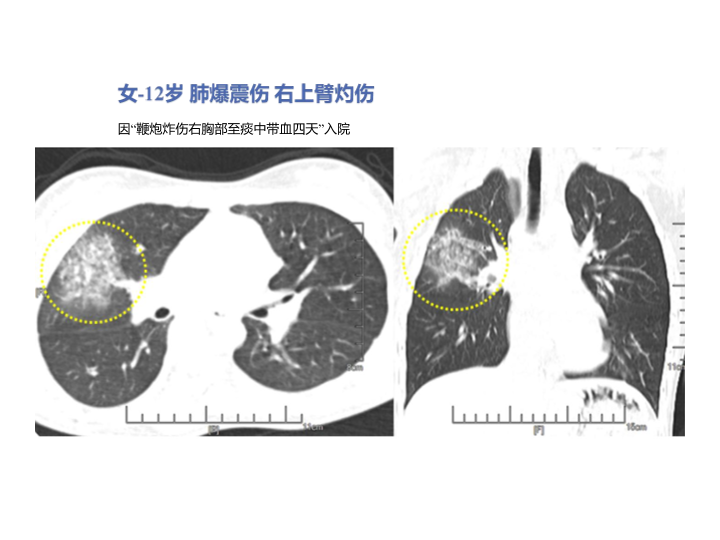

胸部外伤及胸腔积液处理